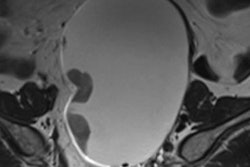

Editor's note: The diffusion-weighted image on the home page of AuntMinnieEurope.com is of a 55-year-old man presenting with right-sided hemiparesis and aphasia. MRI shows a relatively small final infarction volume. Image courtesy of Dr. Wolfgang Kunz, Institute of Clinical Radiology at Ludwig Maximilian University of Munich.